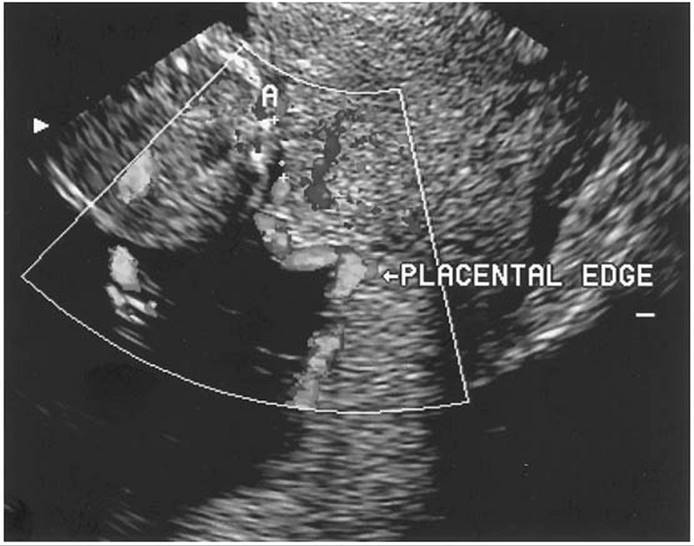

Although initially thought to be contraindicated in patients with suspected placenta previa, transvaginal scanning can be safely performed with caution. In many cases, the relationship between the placental edge and the internal os can be difficult to assess and only a close-up view with a transvaginal approach can make a definitive diagnosis (Fig. 20.3). This approach to scanning has been studied carefully and it does not appear to lead to increased vaginal bleeding, in part because it is technically impossible to introduce the probe through the cervix. Another alternative approach is with translabial scanning which has been reported to be 100% sensitive for detection of a previa. However, on occasion, bowel gas can interfere. When a clear diagnosis of placenta previa is made by a transabdominal or translabial scan, there is no need to perform a transvaginal scan. However, when a partial/marginal placenta previa or low-lying placenta is suspected, a transvaginal scan should be performed to confirm the diagnosis and the distance between the internal os and lower placental edge should be determined. Both types of scanning have greatly reduced the false-positive rate by transabdominal scanning alone which is reported to be as high as 25%.

FIG. 20.3. A transvaginal ultrasound image of a complete placenta previa. The arrow points to the internal os. P, placenta; B, bladder.